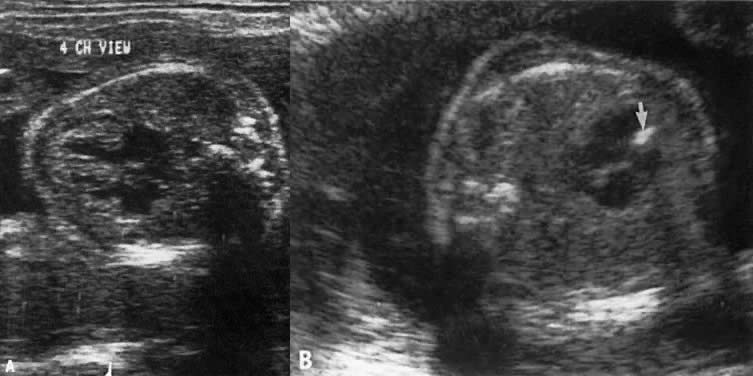

The ultrasonographer should obtain a number of views of the four chambers to gain adequate visualization of all these structures (Fig. 3).

Fig. 3. These echograms illustrate the need to obtain a number of four-chamber views of the heart. A. Echogram of four-chamber view showing equal-sized ventricles of normal thickness, a moderator band in the right ventricle (arrow), a normal-looking interventricular septum, and a normal septum primum. The septum secundum is not apparent. B. A second four-chamber view in same patient clearly shows septum primum and secundum, but the moderator band is not clear.